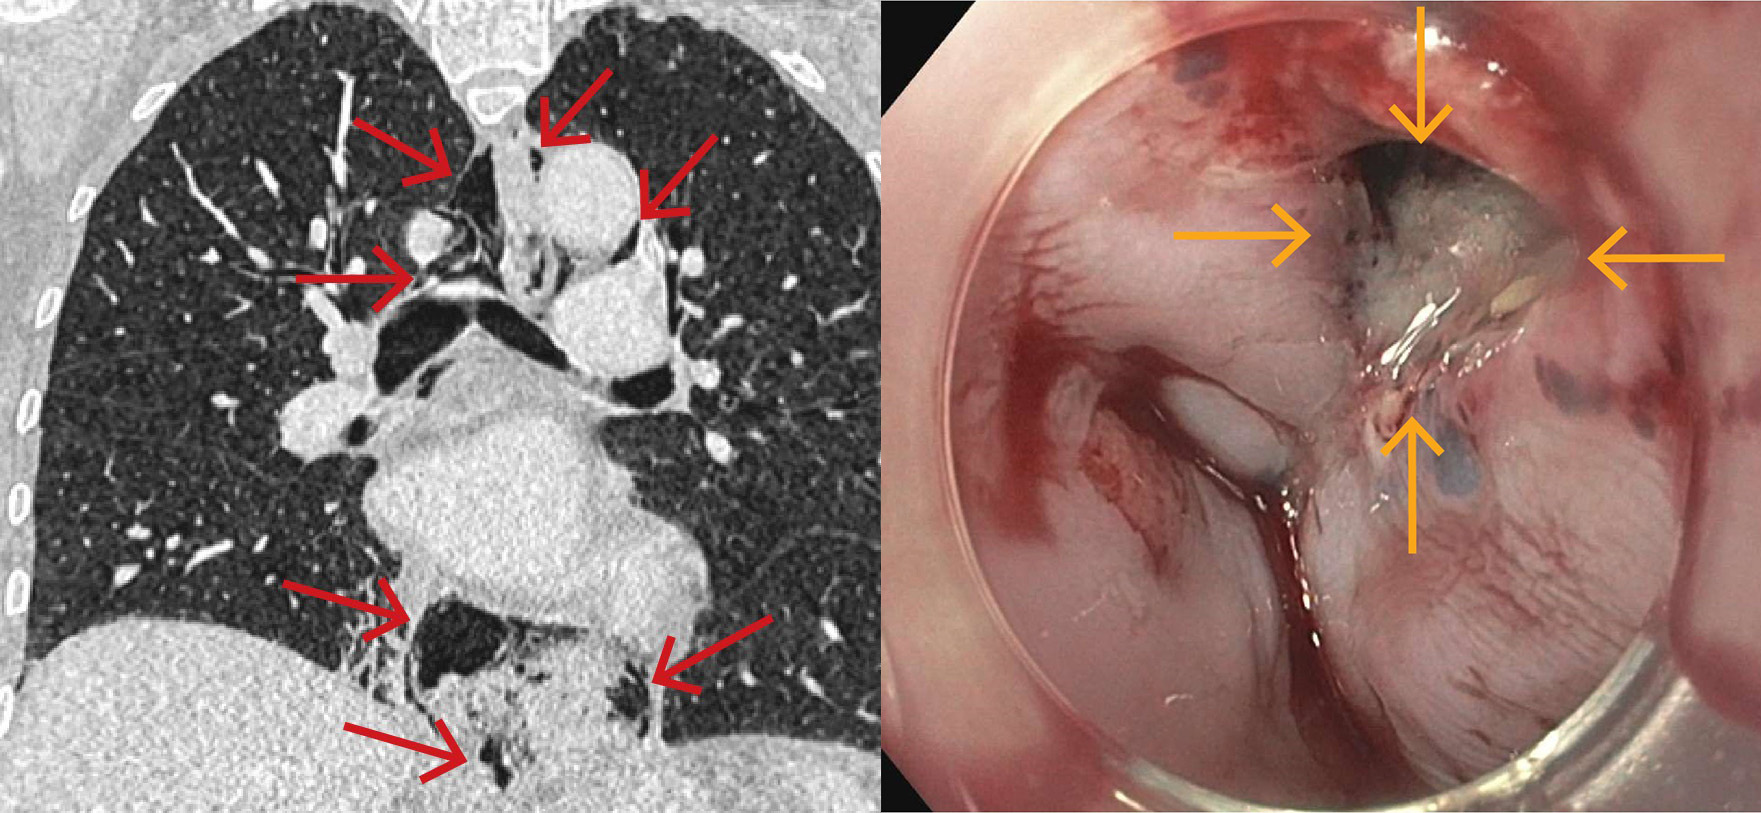

På grunn av uavklarte smerter ble kvinnen undersøkt med CT toraks, abdomen og bekken med intravenøs kontrast. Undersøkelsen viste spredte små luftlokulamenter i bløtdeler på hals, i mediastinum, langs øsofagus og i øvre abdomen i tilslutning til cardia ventriculi (figur 1). Hun hadde også beskjedne mengder pleuravæske bilateralt og beskjedne fortetninger deklivt i høyre underlapp.